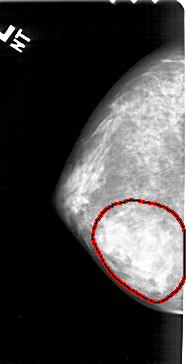

A_1379_1.LEFT_MLO

LEFT_MLO LINES 5041 PIXELS_PER_LINE 2596 BITS_PER_PIXEL 12 RESOLUTION 43.5 OVERLAY

FILE: A_1379_1.LEFT_MLO.OVERLAY

TOTAL_ABNORMALITIES 1

ABNORMALITY 1

LESION_TYPE MASS SHAPE IRREGULAR MARGINS ILL_DEFINED

ASSESSMENT 4

SUBTLETY 4

PATHOLOGY BENIGN

TOTAL_OUTLINES 1

BOUNDARY